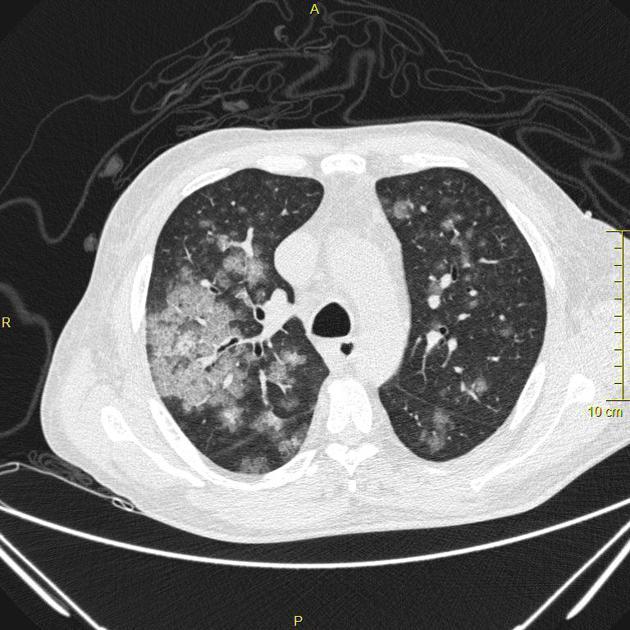

HOMEM, 50 ANOS, INTERNADO POR DISPNEIA + HEMOPTISE DE INÍCIO SÚBITO

áreas de opacidade em vidro fosco associadas a espessamento de septos interlobulares e intralobulares

HEMORRAGIA PULMONAR